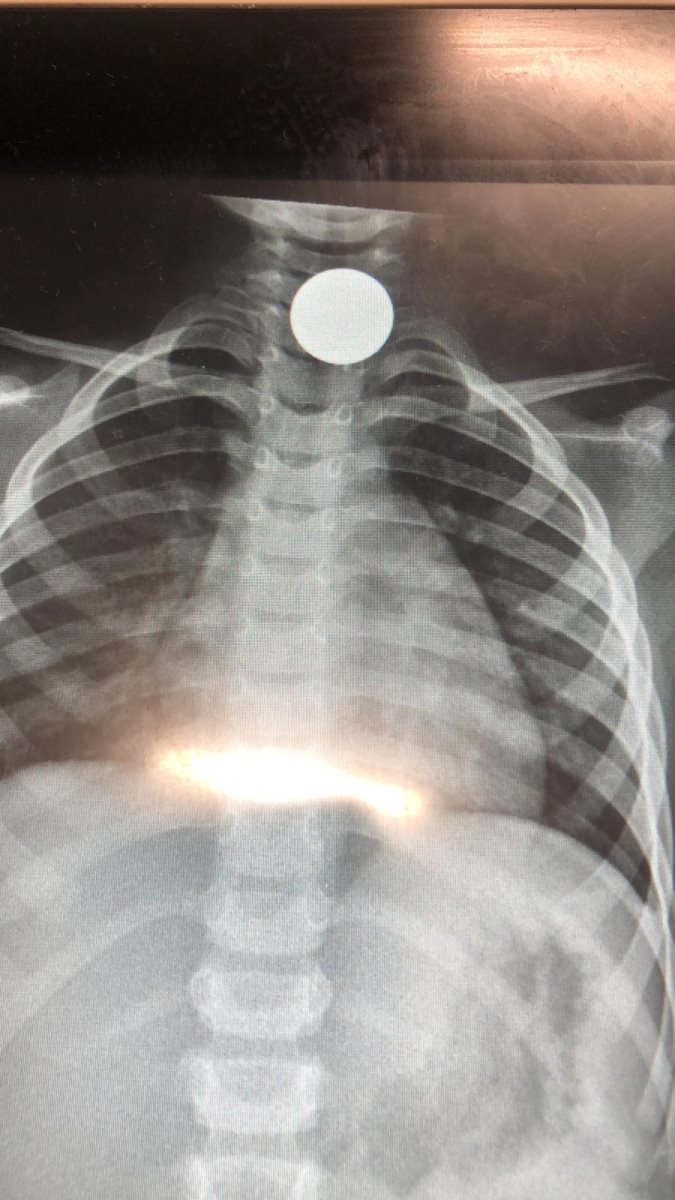

עם קבלתו במיון, בוצע צילום רנטגן בו נמצא כי המטבע הגיע לושט במקום רגיש ומסוכן. עידן הצעיר הובהל לחדר הניתוח ושם הוצא המטבע (חצי שקל) בהצלחה ע"י ד"ר יהודה שוורץ - הרופא המנתח, וד"ר סעיד אברהים הרופא המרדים. לאחר מכן הוא הועבר להמשך טיפול והשגחה במחלקת ילדים.